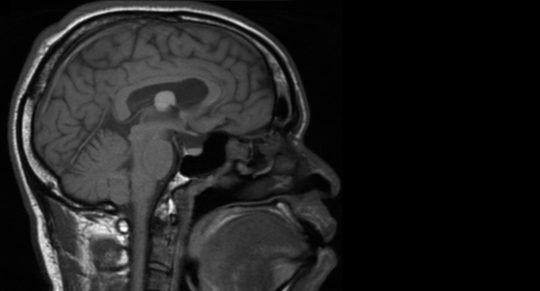

cycst-cleaned

Matthew

"I used to think that life is competitive, but that's not true"